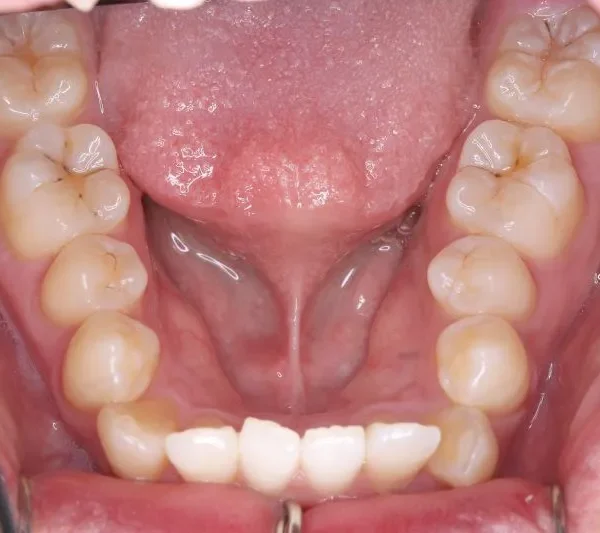

• 初診

初診時年齢 19~29歳 (女性) 主訴 ガタガタ・交叉咬合が気になる

診断名 叢生・交叉咬合 装置名

ガタガタ・八重歯を主訴に来院された患者様です。

頬杖をする癖がおありでした。

初診